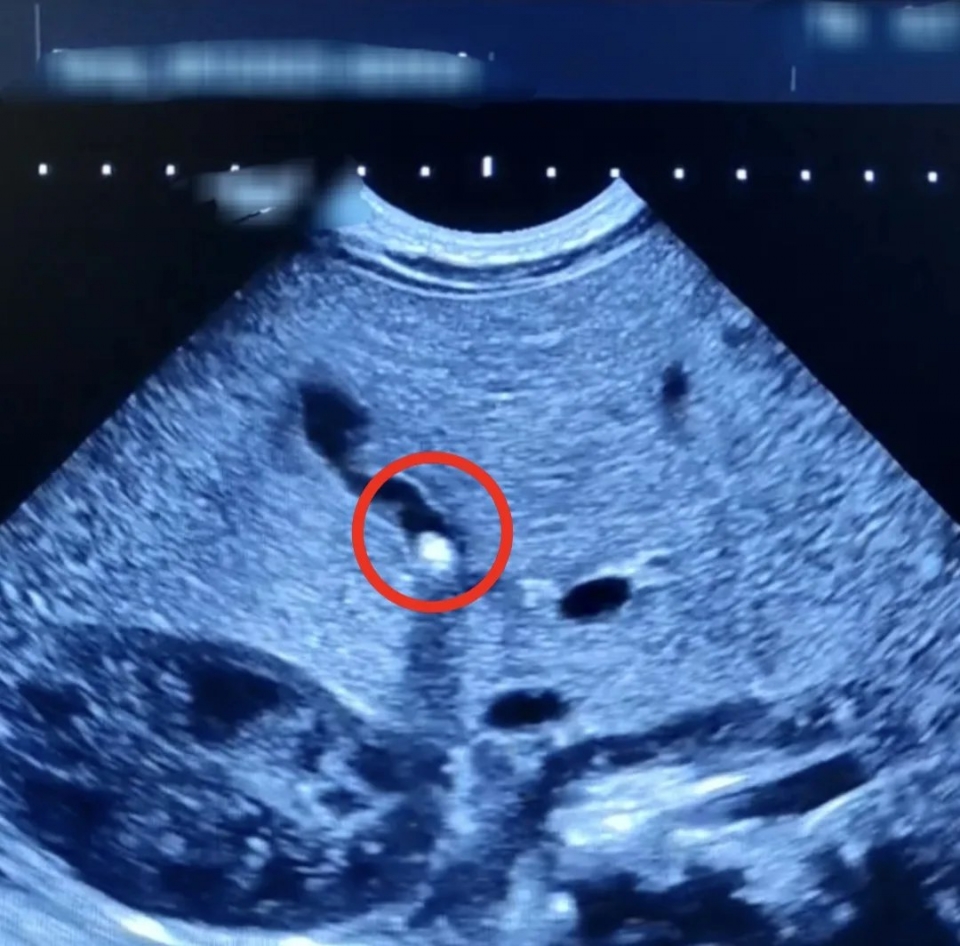

А в этом месяце подобный недуг, правда, не в такой тяжелой форме диагностировали уже у младенца. Его выявили при проведении УЗИ брюшной полости – врачи обнаружили камушек в желчном пузыре.

Ребенок поступил в стационар с жалобами мамы на плохую прибавку массы тела и желтушное окрашивание кожи и склер. При обследовании выяснилось, что желчный проток частично закрыт камнем небольших размеров. Врачам удалось не только улучшить отток желчи из желчного пузыря, но и добиться стабильной прибавки в весе, которой не наблюдалось в первый месяц жизни ребенка. Сейчас пациент выписан домой и находится на амбулаторном наблюдении.